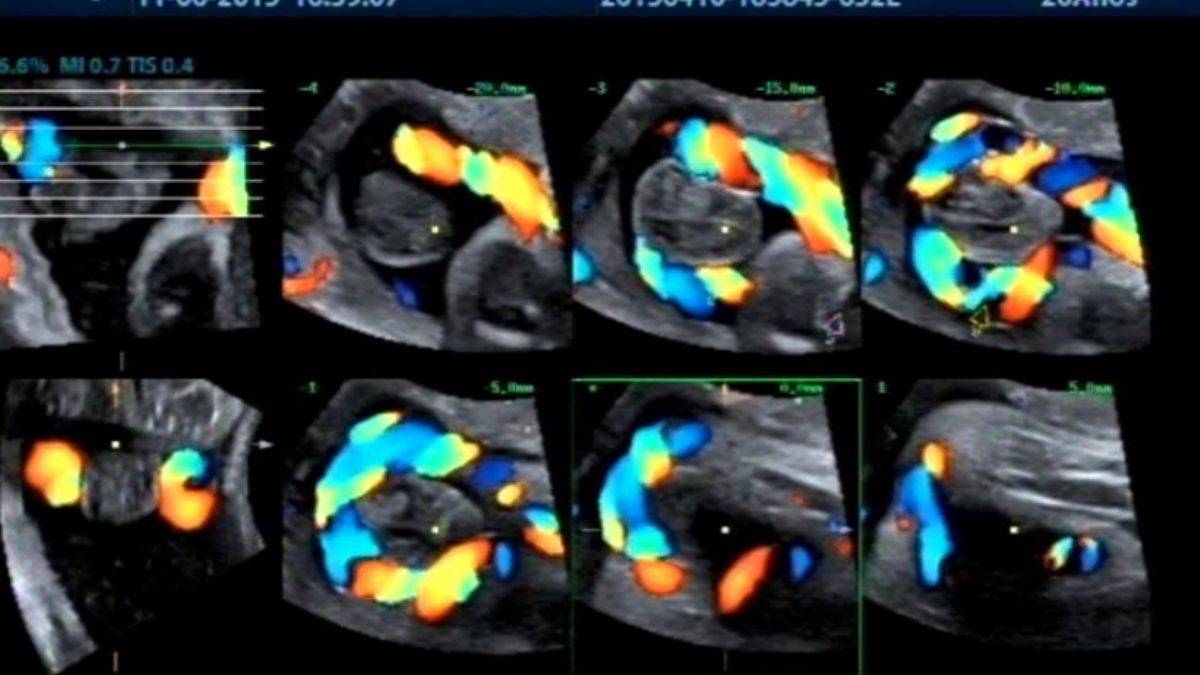

Renkli Doppler Nedir?

Ultrasonografi yönteminin destekleyicisi olarak kullanılan renkli doppler iç organların, damarların ve kitlelerin incelemesi amacıyla kullanılır.

Günümüzde, sıklıkla kullanılan bir yöntemdir. Kan akışının niteliği ve niceliği ile ilgili bilgi edinmek ve bir sorun olup olmadığını anlamak amacıyla başvurulan bir yöntem olan renkli doppler birçok hastalığın tespitinde etkilidir.

Mavi ve kırmızı renklerin kullanıldığı renkli doppler yönteminde önce gri skala ile bir tarama yapılır. Gri ultrasonografi ile orantılı olarak kullanılan renkli doppler akışın net bir şekilde izlenmesi için renkli olarak görüntülenir. Radyoloji uzmanı tarafından çekilen renkli doppler anında sonuçlanır.

Renkli Doppler Hangi Alanlarda Kullanılır?

Kullanım alanı oldukça geniş olan renkli doppler en fazla hamilelikte bebeğin gelişimi ve annenin sağlığı açısından kullanılır. Kadınlarda genital organ incelenmesinde, kol ve bacak damarlarında, hipertansiyon, boyun damarlarının incelenmesinde de sıklıkla başvurulur.